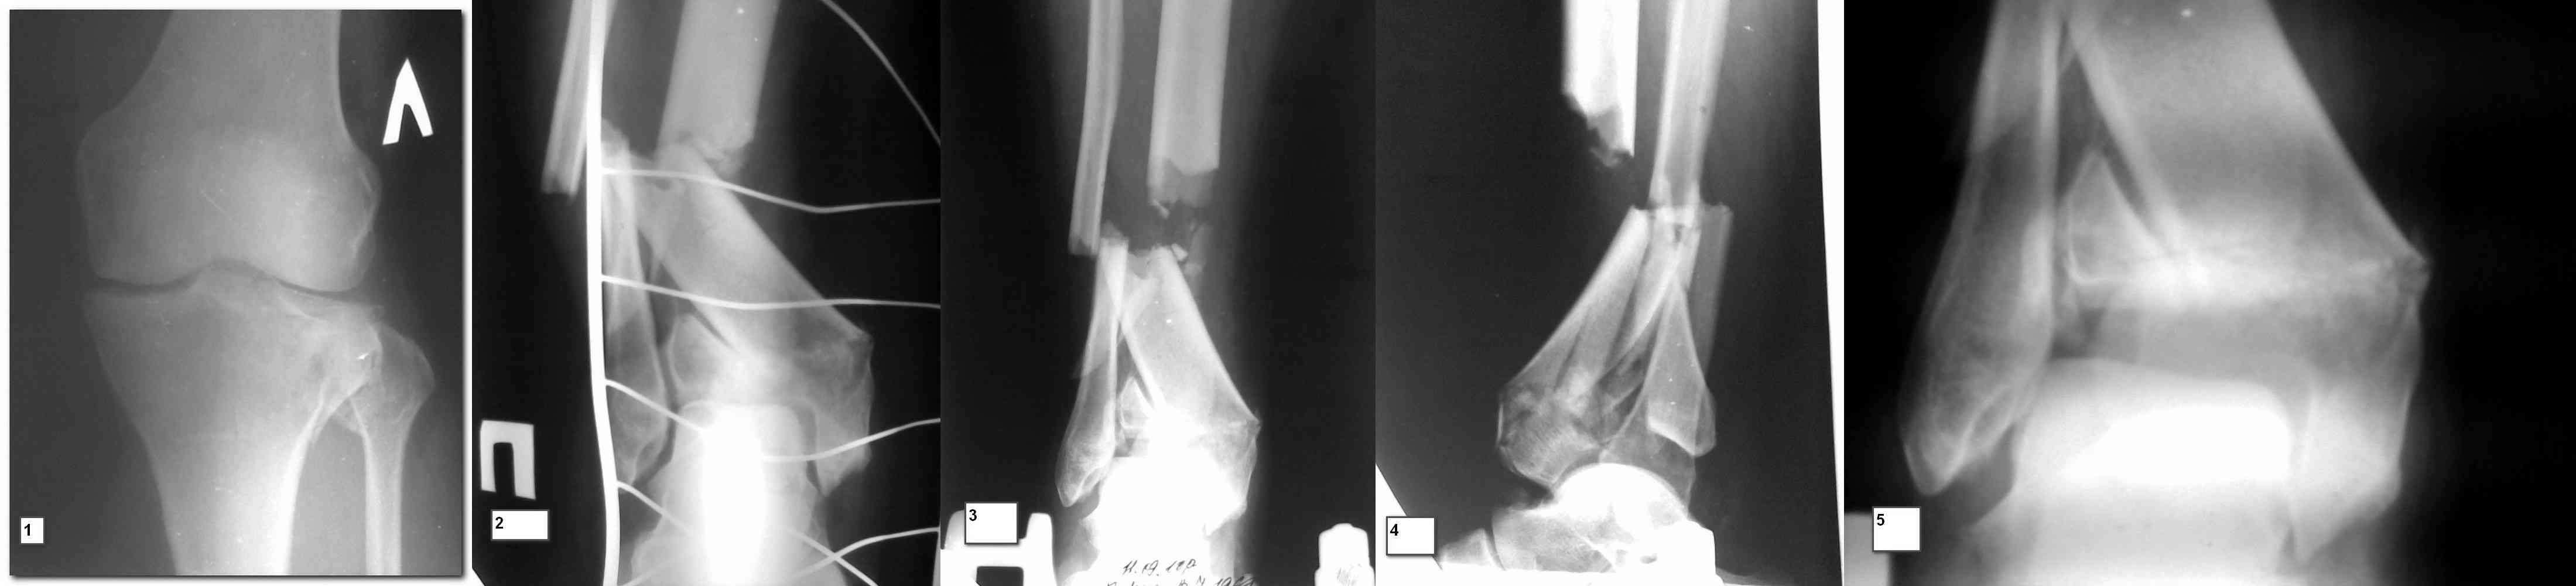

Диагноз: закрытый внутрисуставный перелом внешнего мыщелка левой большеберцовой кости со смещением. Закрытый внутрисуставный многооскольчатый перелом нижней трети и дистального метаэпифиза правой большеберцевой кости со смещением.

На коже в области внутренней лодыжки правой голени эпидермальный пузырь с прозрачной жидкостью до 3.5 см в диаметре, сразу под кожей пальпируется костный фрагмент, в остальном кожа нормальная. Отёка нет. Находится на скелетном вытяжении с весом 6 кг за правую пятку.

Рентгенограммы:

1. левый коленный сустав

2. правая голень при поступлении (9.09)

3. правая голень на вытяжении 6 кг (11.09)

Предварительно планируем подержать на вытяжении до заживления кожи в области пузыря. Переде-медиальным доступом открыть место перелома и суставную поверхность, репозиция промежуточного отломка по центральному, низвести шилом закрыто задний фрагмент суставной поверхности, фоксировать винтом в сагиттальной плоскости, после чего пластина-мост по медиальной поверхности с отдельными винтами или спицами для фиксации отломков суставной поверхности. Адекватной стабильности вряд ли удастся добиться – гипсовая повязка.